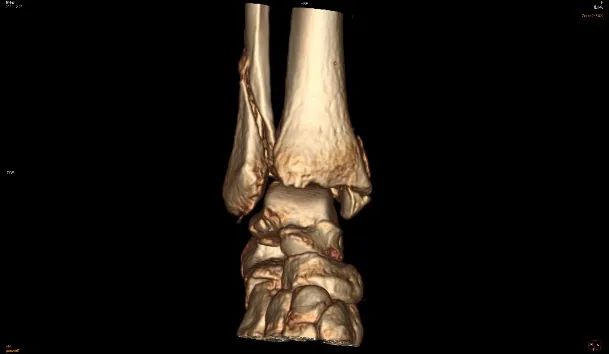

CT检查是多层断面成像,对于细微骨折、复杂部位骨折是强项

CT全称为计算机X线断层扫描,是一种常用的影像学检查方法。先由X线照射一定厚度的人体组织,然后通过接收器接收穿过该组织的X线,并将其转化为电信号和数字信号,最后通过计算机处理形成CT图像,具有较高的分辨率。CT检查可以从任意方向对图像进行二维重建和三维立体重建,避免骨头前后重叠造成的误解影像,并且能很好显示骨折线的走行、累及关节面情况,能够更好地评价骨折的严重程度。因此,对于某些特殊部位的细微骨折、需要进一步观察骨折线累及关节面情况、评估骨折严重程度的骨折,则需要进一步CT检查。